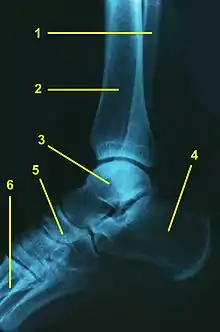

III. Examenul radiologic:

Glezna poate fi examinată radiologic cu ajutorul radiografiilor standard și, dacă este nevoie, și cu cel al radiografiilor dinamice.

- Radiografiile standard sunt următoarele:

- radiografia antero-posterioară a gleznei cu rotația internă de 20 de grade:

Pe această incidentă pot fi observate eventualele fracturi asociate entorsei acute sau modificări artrozice în instabilitatea cronică a gleznei. De asemenea, permite vizualizarea interliniei articulare și mai ales a unghiului supero-lateral al domului talar care poate fi sediul unei fracturi osteocondrale (afectarea unghiului supero-medial este mai rară).

- radiografia laterală a gleznei:

Poate arăta o mica smulgere osoasă la nivelul colului talar, semn al unei entorse grave și interlinia articulară talo-naviculară, la nivelul căreia pot fi uneori prezente mici fracturi prin avulsie, traducând și ele gravitatea entorsei.